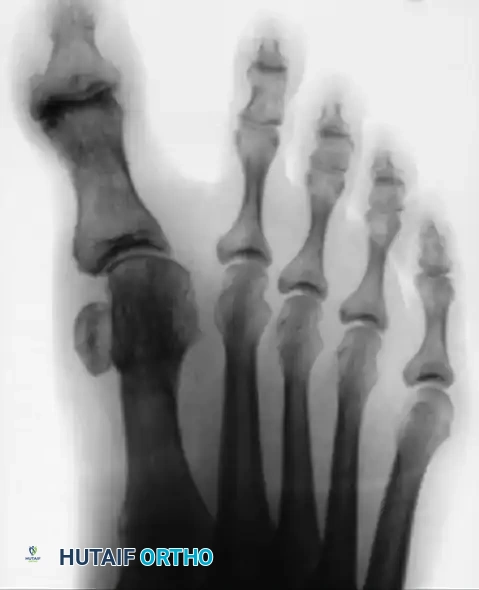

CORRECTION OF DYNAMIC (MULTIPLANAR) HALLUX VARUS Surgical Diagram

Preoperative radiograph of a middle-aged woman demonstrating a severe multiplanar hallux varus deformity (clawed hallux) with medial subluxation of the MTP joint.

Postoperative radiograph of the same patient demonstrating correction of the multiplanar hallux varus deformity via resection arthroplasty. The joint is decompressed, and the axial alignment is restored.